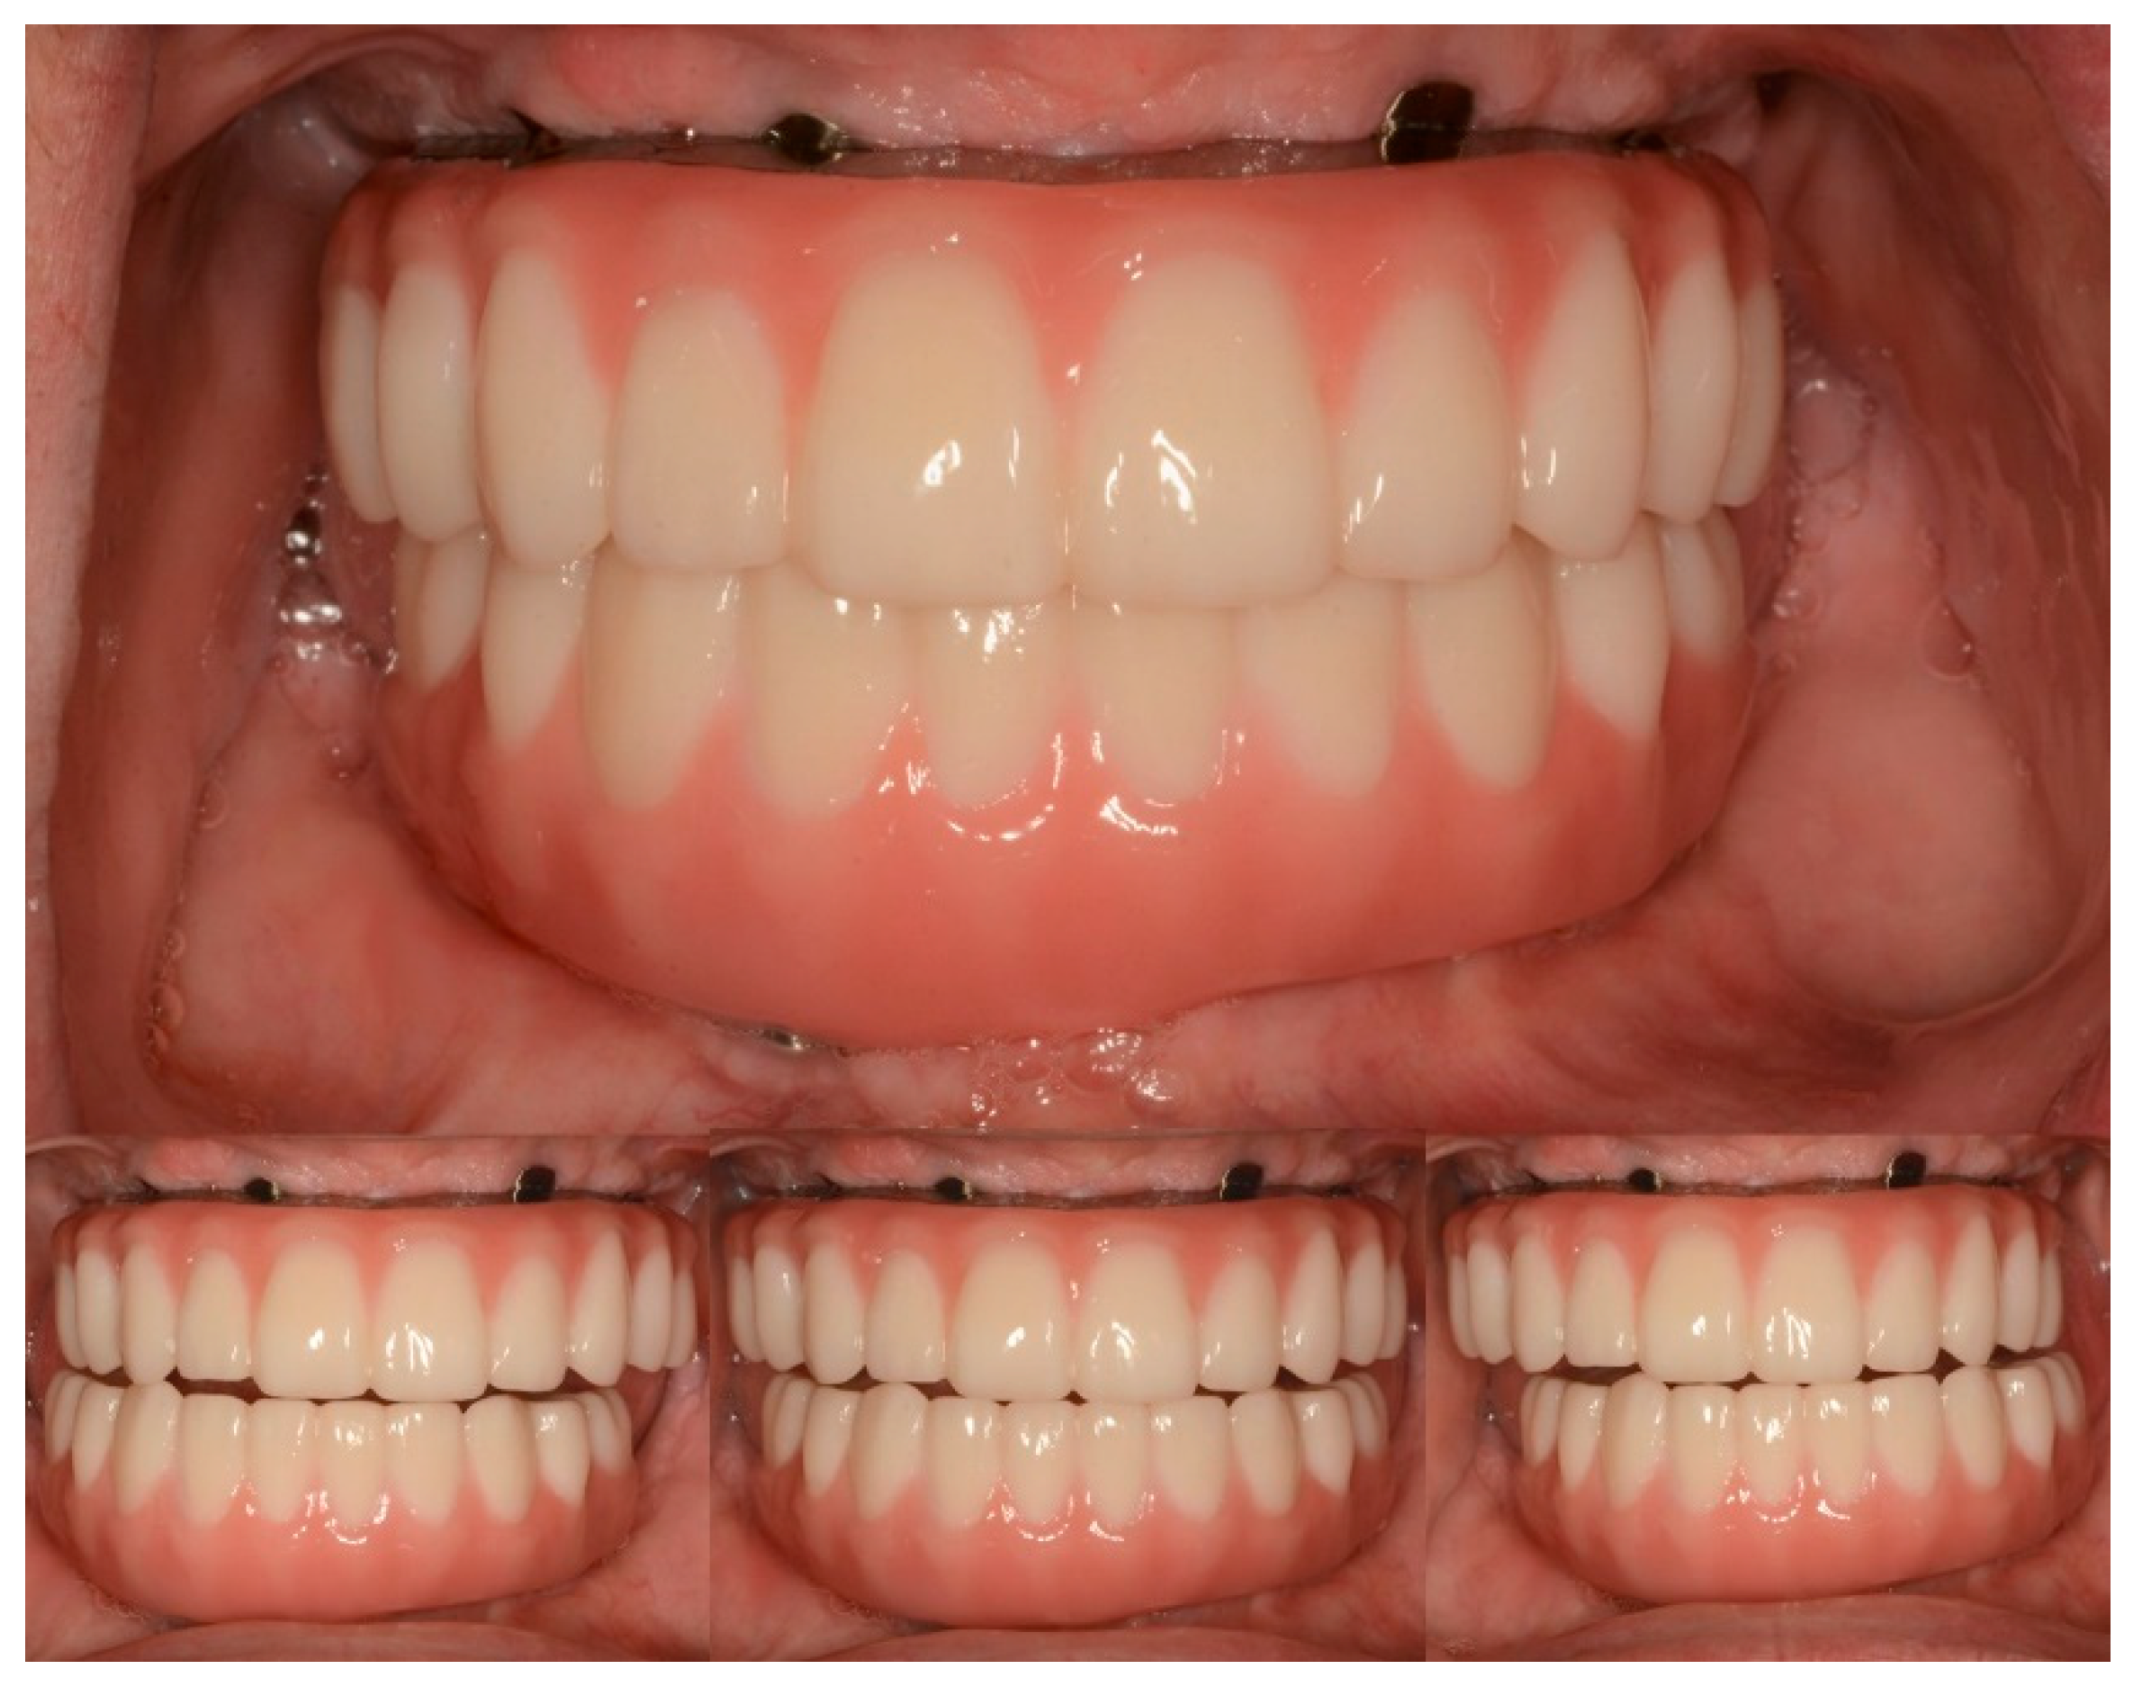

Vertical dimension, centric occlusion, protrusive, and laterotrusive excursive movements were assessed and refined (Figure 11). Additionally, cleanability, esthetics, and comfort were deemed adequate by the patient (Figure 11).

Figure 11.

Intraoral photograph of maxillary and mandibular definitive complete-arch implant-supported prostheses. (Top) Centric occlusion. (Bottom) Lateral and protrusive excursions.

Subsequently, home maintenance instructions and interdental brushes (ProxaBrush Go-Betweens Wide; GUM Sunstar America, Schaumbaum, IL, USA) were provided, and a hygiene program consisting of recall appointments every 6 months was established on the day of delivery. At the subsequent appointments, overall hygiene was reassessed and deemed adequate. Additionally, during these appointments, the patient expressed satisfaction with the function, esthetics, and confidence provided by the definitive prostheses (Figure 12).